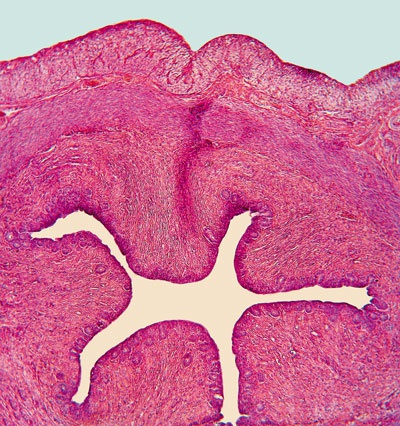

Рис. 13. Стократное увеличение поперечного среза уретры